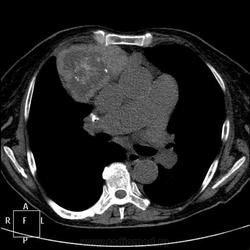

Пациентке 79 лет. Заказана рентгенография ОГК перед операцией (механическая желтуха, камень холедоха). Что скажете, уважаемые коллеги?

Думаю, что интригу с таким какчеством репродукций не создать. Так что пошла закачивать КТшки. Пациентка уже лечилась в мае 2011 по поводу ЖКБ. Тогда же выявлено образование средостения, динамики от сегодняшнего снимка нет. Сколько лет не проходила ФЛГ - неизвестно. Исследования ОГК проводились не мной, разрешение на демонстрацию КТ любезно предоставленно моим коллегой.

До КТ по обзорному снимку в передней прямой проекции - тимома (бугристые, четкие контуры). По боковому - тератома (овальной формы, контуры четкие, ровные, соответствуещее положение). После КТ - тератома (неоднородная структура, плотные включения высокой интенсивности). Думаю еще об одной патологии, но слишком низко расположена. Был хороший повод ещё раз прочитать пособие, вспомнить средостение и т.д. Девиз: больной...книга...анализ...больной в действии. С уважением Nik

И поговорим)): расширение верхнего средостения+бугристая здоровая такая штука в переднем средостении от дуги аорты до 5-го переднего межреберья. Что в сумме получается?

Загрудинный здоровенный зоб...осталось увидеть только перешеек, связывающий его с основной массой щитовидки....

А что, вариант интересный, "оно" 18х9х7 см ниже кажущегося или имеющегося перешейка. Но это не почечная паренхима, ИМХО)). Я могу судить только по структуре и плотности, раз не было контрастирования. И назвала "это" диффузно-узловым зобом с загрудинным распространением. Довольно трудно судить без контрастирования, без верификации, но я свой выбор сделала)). Пара картинок и к вечеру закачаю видео - может, еще идеи возникнут? Или ясности прибавится

Собственно, если быть уж до конца академичным - тогда это не загрудинный зоб, а ВНУТРИГРУДНОЙ зоб, такое в классификации тоже сеть.

Я клоню к тому же: здесь два узла. И за- и внутри-.

Скиалогически - да, два узла; если это зоб, то - внутригрудной (что без загрудинного невозможно даже теоретически

); если два образования, то загрудинный зоб+ неизвестное новообразование переднего средостения. Как верифицировать, вот в чем вопрос?

Еще дело в том, что эти два образования, щитовидную железу и очень сходное по структуре внутригрудное (Вы правы, не загрудинный) образование, разделяют сосуды, и как мне показалось, связь в виде перешейка имеется. Но, наверное, не настолько это и важно. Пока видео не работает, там эту связь можно проследить.